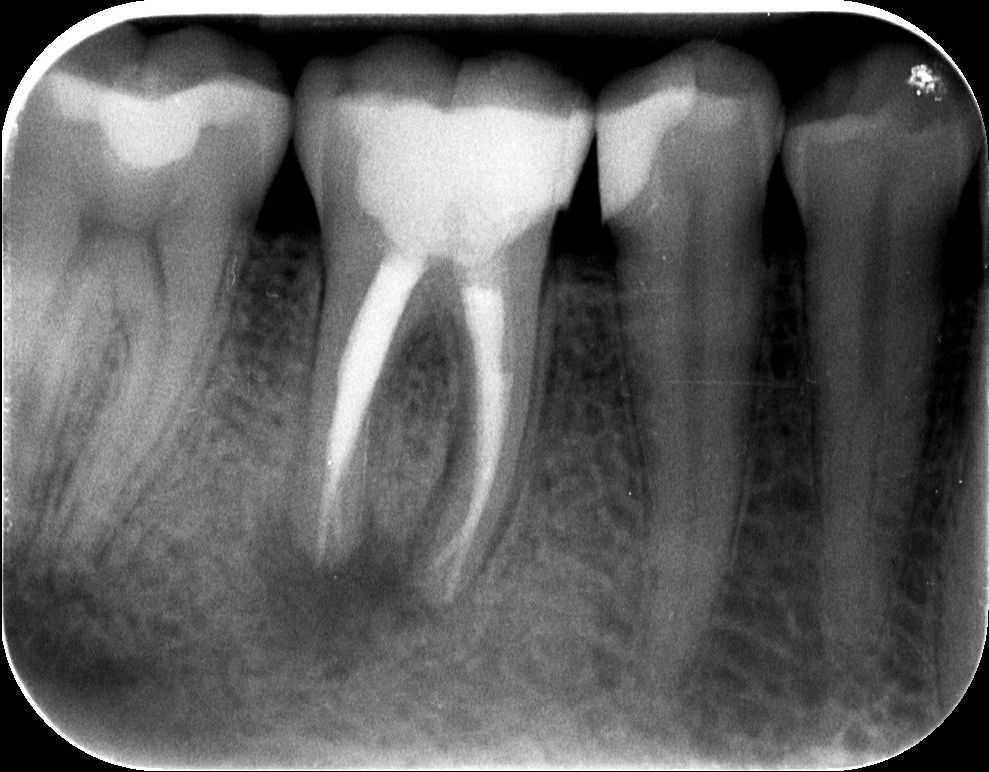

3. röntgenfelvétel

Az alábbi felvételen látható a kész gyökértömés első szakasza, amikor a gyökértömés alsó harmadát készítjük el meleg guttapercha-technikával. A kiindulási röntgenfelvétellel összehasonlítva látható, hogy a gyökértömő anyaggal szépen sikerült elérni a gyökércsúcsok végéig.